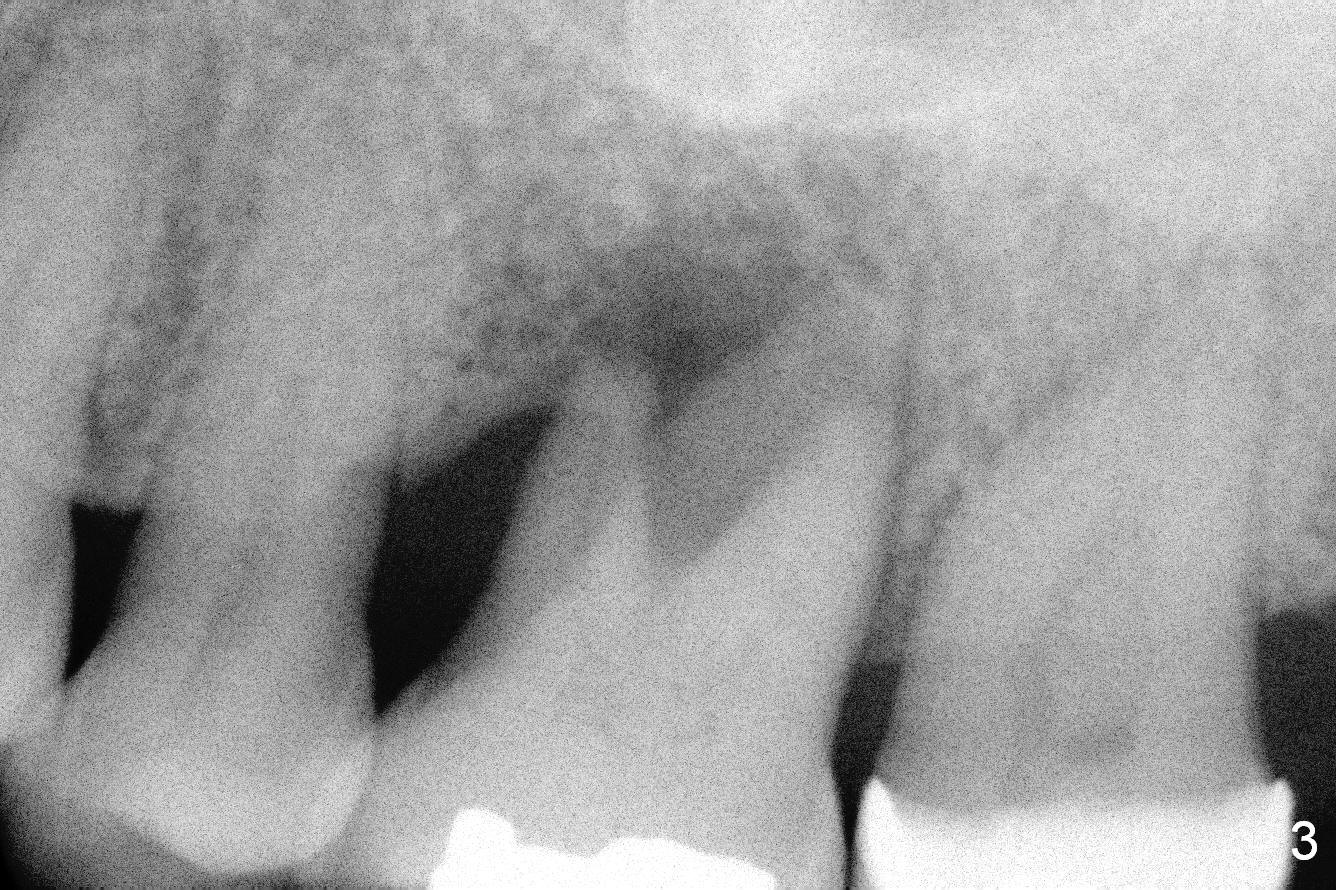

A 54-year-old woman has history of chronic periodontitis with bruxism. Bone loss at the tooth #14 starts at the mesial crest (Fig.1: 2008), extends to the mesial root (Fig.2, 2015) and the palatal one (Fig.3, 2016). The periodontal pockets are deep with mobility III. Since the defect is large with low bone density, Magic osteotomes are going to be used for CMC immediately after extraction (Clindamycin). If there is no history of sinusitis, a 11 mm long implant will be placed (Fig.4). Allograft (.5-1.5 mm) will be delivered with the large bone carrier for CMC (prior to implant placement) and the amalgam carriers for socket gap closure (before and after implant placement).